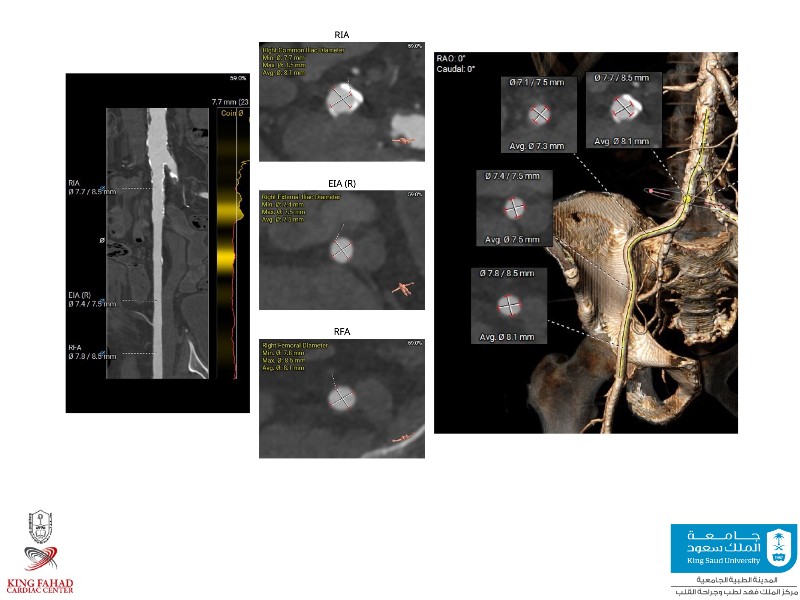

This session helps you anticipate and address complex scenarios such as mitral valve-in-valve, TAV-in-SAV, and valve-in-valve-in-valve procedures. Learn from expert case discussions that explore procedural strategies, technical challenges, and best practices to optimize outcomes in redo structural heart interventions.

- To anticipate and manage second valve scenarios with SAPIEN 3 Ultra RESILIA, including mitral valve-in-valve, TAV-in-SAV, and TAV-in-TAV

- To understand procedural strategies and challenges in complex redo scenarios using SAPIEN 3 Ultra RESILIA